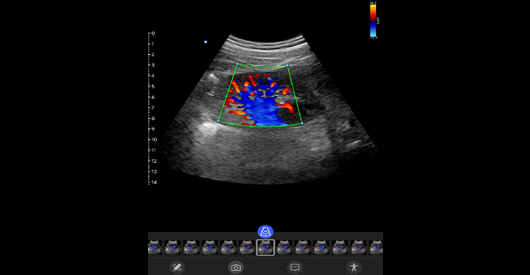

肾脏血流

中⼼频率:3.6 MHz。带宽范围:2-5MHz。